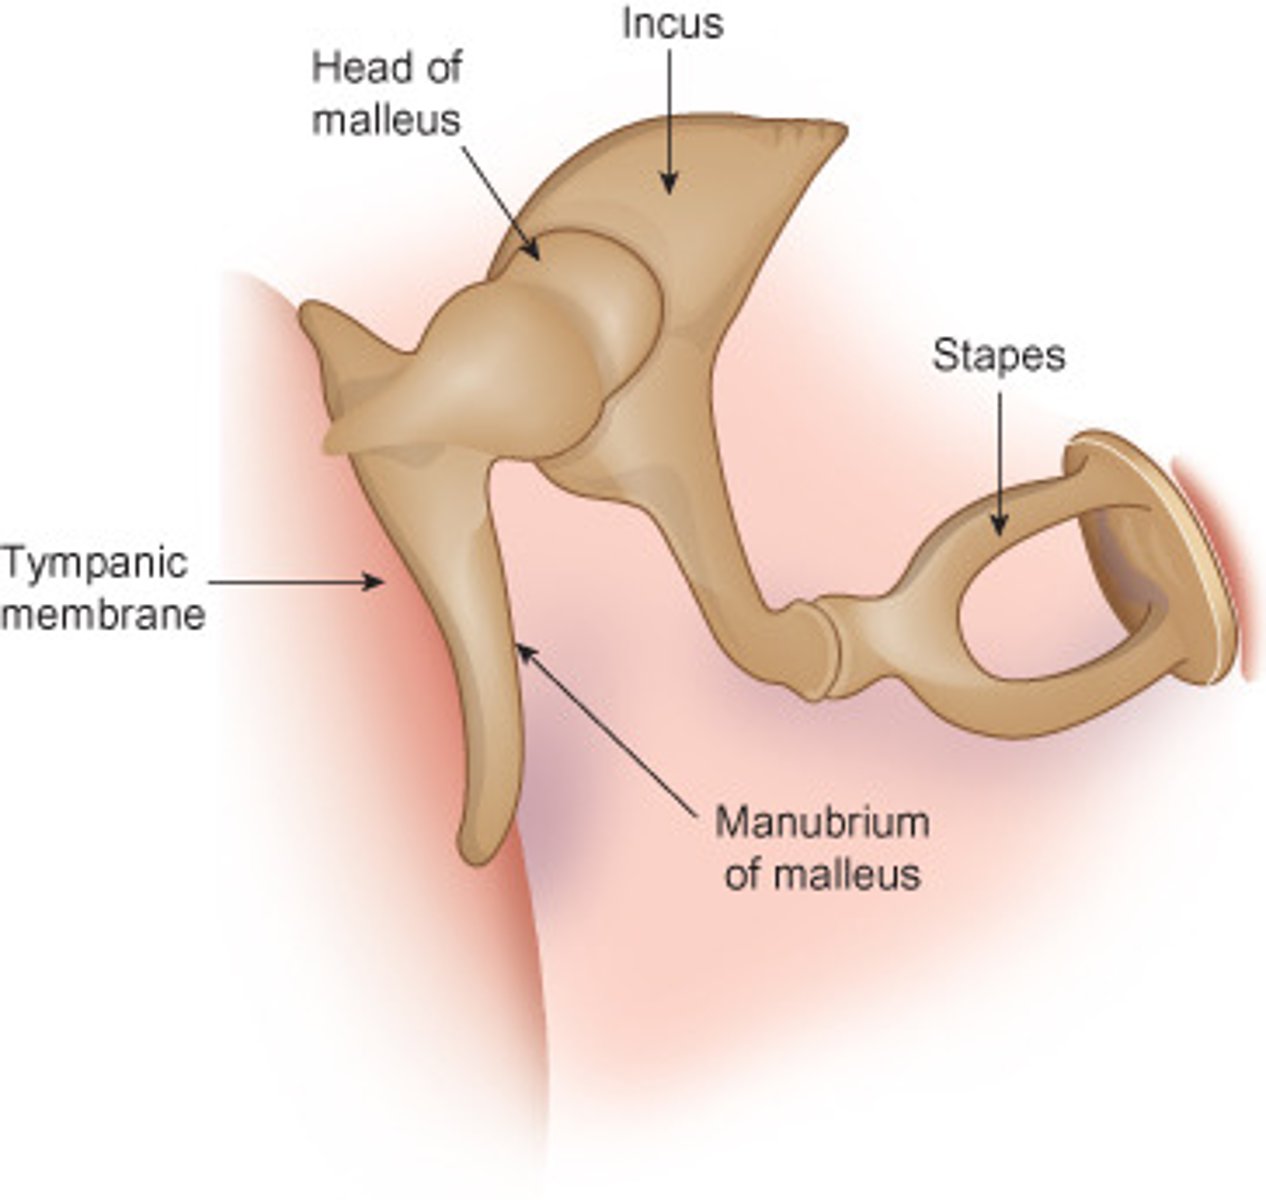

ear ossicles

malleus, incus, stapes